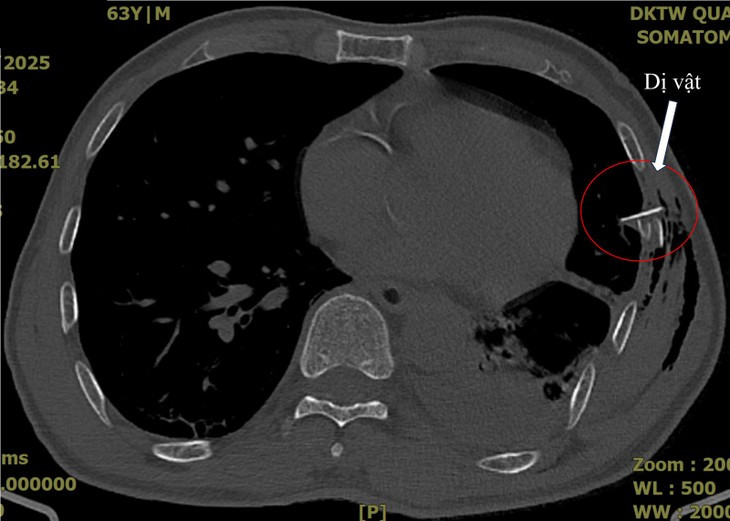

| Hình ảnh chụp cắt lớp ngực của bệnh nhân V.Đ.Q. ghi nhận tràn khí, tràn máu màng phổi với một mảnh xương sườn đâm vào nhu mô phổi - Ảnh BVCC |

Sau đó, bệnh nhân có cơn đau ngực tăng dần, đau không dám thở, trong tình trạng suy hô hấp, hình ảnh X-quang phổi chưa ghi nhận bất thường khác ngoài gãy các xương sườn VI, VII, VII. Bệnh nhân được chụp cắt lớp ngực và ghi nhận tràn khí, tràn máu màng phổi với một hình ảnh mảnh xương sườn đâm vào nhu mô phổi.